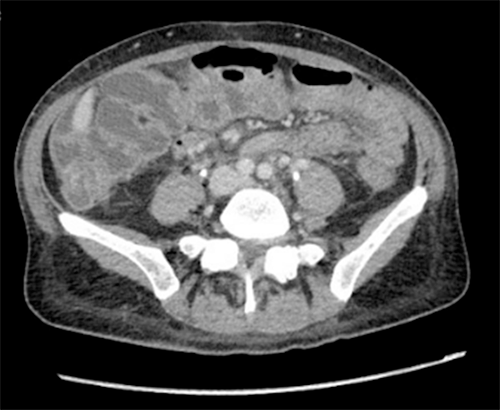

Figure 1. Axial Images of Abdomen Demonstrating Retroperitoneal Fibrosis. Published With Permission

A) CT abdomen/pelvis with IV contrast at time of diagnosis of RPF, with encasement notably visible at the level of the aortic bifurcation; B) PET/CT showing diffuse uptake throughout retroperitoneum (arrow indicating right hydronephrosis and hydroureter); C) CT abdomen/pelvis with IV contrast seven weeks after initial CT, revealing interval increase in RPF, at level superior to aortic bifurcation.

The patient was referred to our surgical oncology clinic for evaluation five weeks after her annual exam. Her interview revealed a history of diarrhea for one year, early satiety for four months, 4.5 kg unintentional weight loss over the past two months, and intermittent LLQ pain radiating to her back for two months. During this appointment, she was scheduled for staging laparoscopy, esophagogastroduodenoscopy/esophageal ultrasound (EGD/EUS), and positron emission tomography/computed tomography (PET/CT) to complete staging. EGD/EUS showed invasion limited to the muscularis propria, indicating stage T2 disease and hyperechoic lesions concerning peritoneal implants and ascites. PET/CT scan showed mild, diffuse gastric wall thickening with mild uptake (SUV 4.8), gastrosplenic lymph nodes larger than 11 mm (SUV 4.7), and a significant increase in ill-defined RP soft tissue extending to bilateral common iliac chains (SUV 3.3) producing new right hydroureteronephrosis extending to the upper pelvis (Figure 1B).